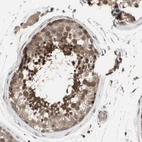

Immunohistochemical staining of human cerebral cortex shows strong cytoplasmic positivity in neurons.